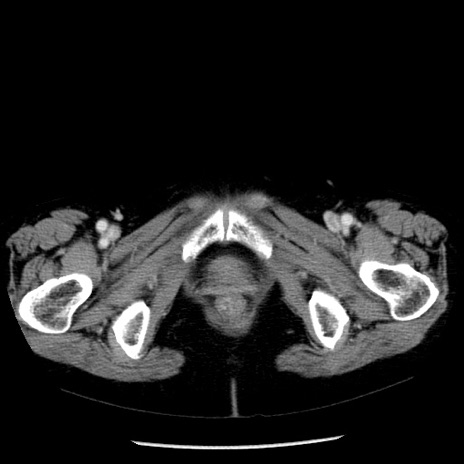

症例13(横断像)

【症例】70歳代女性

【主訴】腹痛、嘔吐

【現病歴】15時間程前(昨晩)より腹痛あり。今朝になっても症状の改善なく、嘔吐あり。腹痛も増悪あり、救急外来受診。

【既往歴】子宮癌全摘術後

【身体所見】意識清明、BP 121/72mmHg、P 74bpm、SpO2 100%(RA)、腹部:平坦・軟、腸雑音ほぼ聴取せず。下腹部・心窩部・臍左上に圧痛あり。反跳痛なし。

【データ】WBC 10600、CRP 0.15